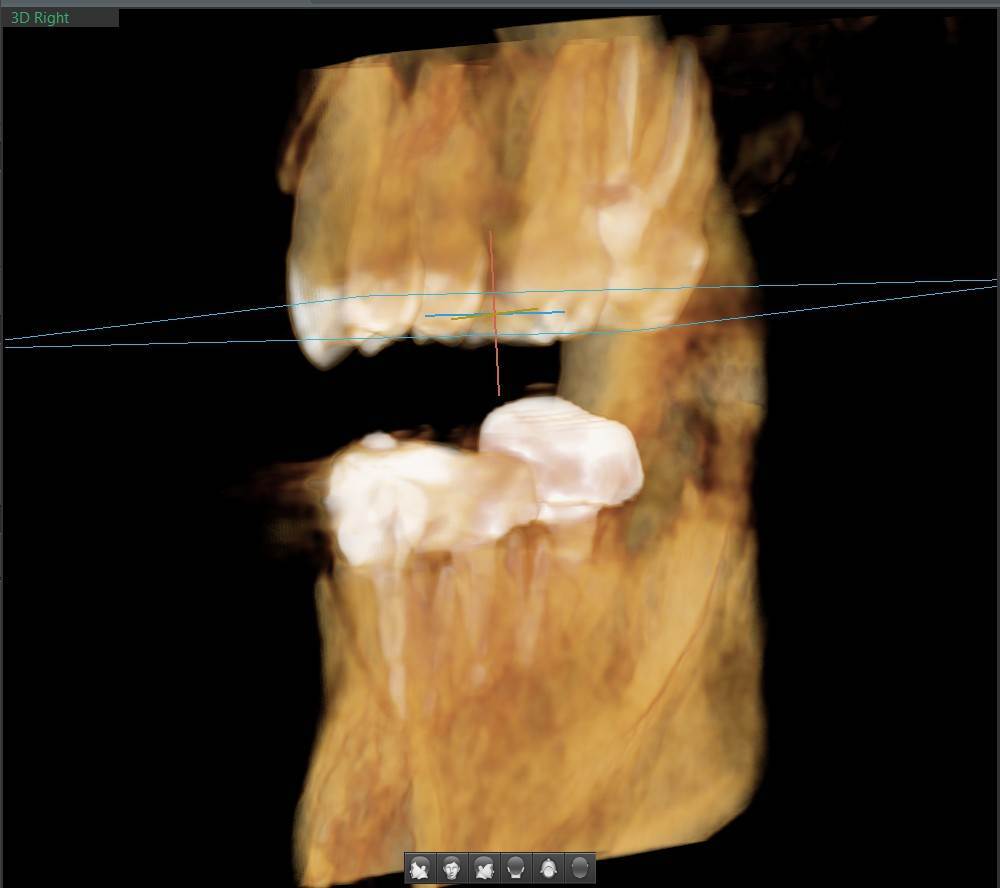

A-V-S Опубликовано 3 марта Поделиться Опубликовано 3 марта Здравствуйте. У меня такая ситуация: В начале января 2026 начал болеть зуб 7ка снизу слева - боль развивалась постепенно - в итоге стало больно жевать. Сделал КТ. Лечащий стоматолог сказал, что это проснулось спящее воспаление, перелечивать каналы зуба сложно - надо сверлить буром и доставать стекловолоконный штифт - надо удалять. В следующие дни открылся свищ и боль ушла. Свищ продолжает быть с периодическим набуханием и сдуванием после выброса гноя белого цвета. Этот зуб лечили с установкой стекловолоконного штифта чуть больше 5 лет назад. Посмотрите, пожалуйста, приложенные снимки и посоветуйте как быть - можно ли перелечить и сохранить зуб ? Ссылка на комментарий

АнтонТЛТ Опубликовано 3 марта Поделиться Опубликовано 3 марта Добрый вечер, лучше выложить несколько срезов этого зуба, либо архив с кт. По представленным снимкам, есть подозрение о наличии трещины между корнями зуба. 1 1 Ссылка на комментарий

Гарриевич Опубликовано 6 марта Поделиться Опубликовано 6 марта Не знаю обрадует Вас это или огорчит, но зуб можно сохранить соседний тоже с воспалением кстати 1 1 Ссылка на комментарий

red_butler Опубликовано 9 марта Поделиться Опубликовано 9 марта В 03.03.2026 в 22:49, A-V-S сказал: можно ли перелечить и сохранить зуб ? можно Ссылка на комментарий